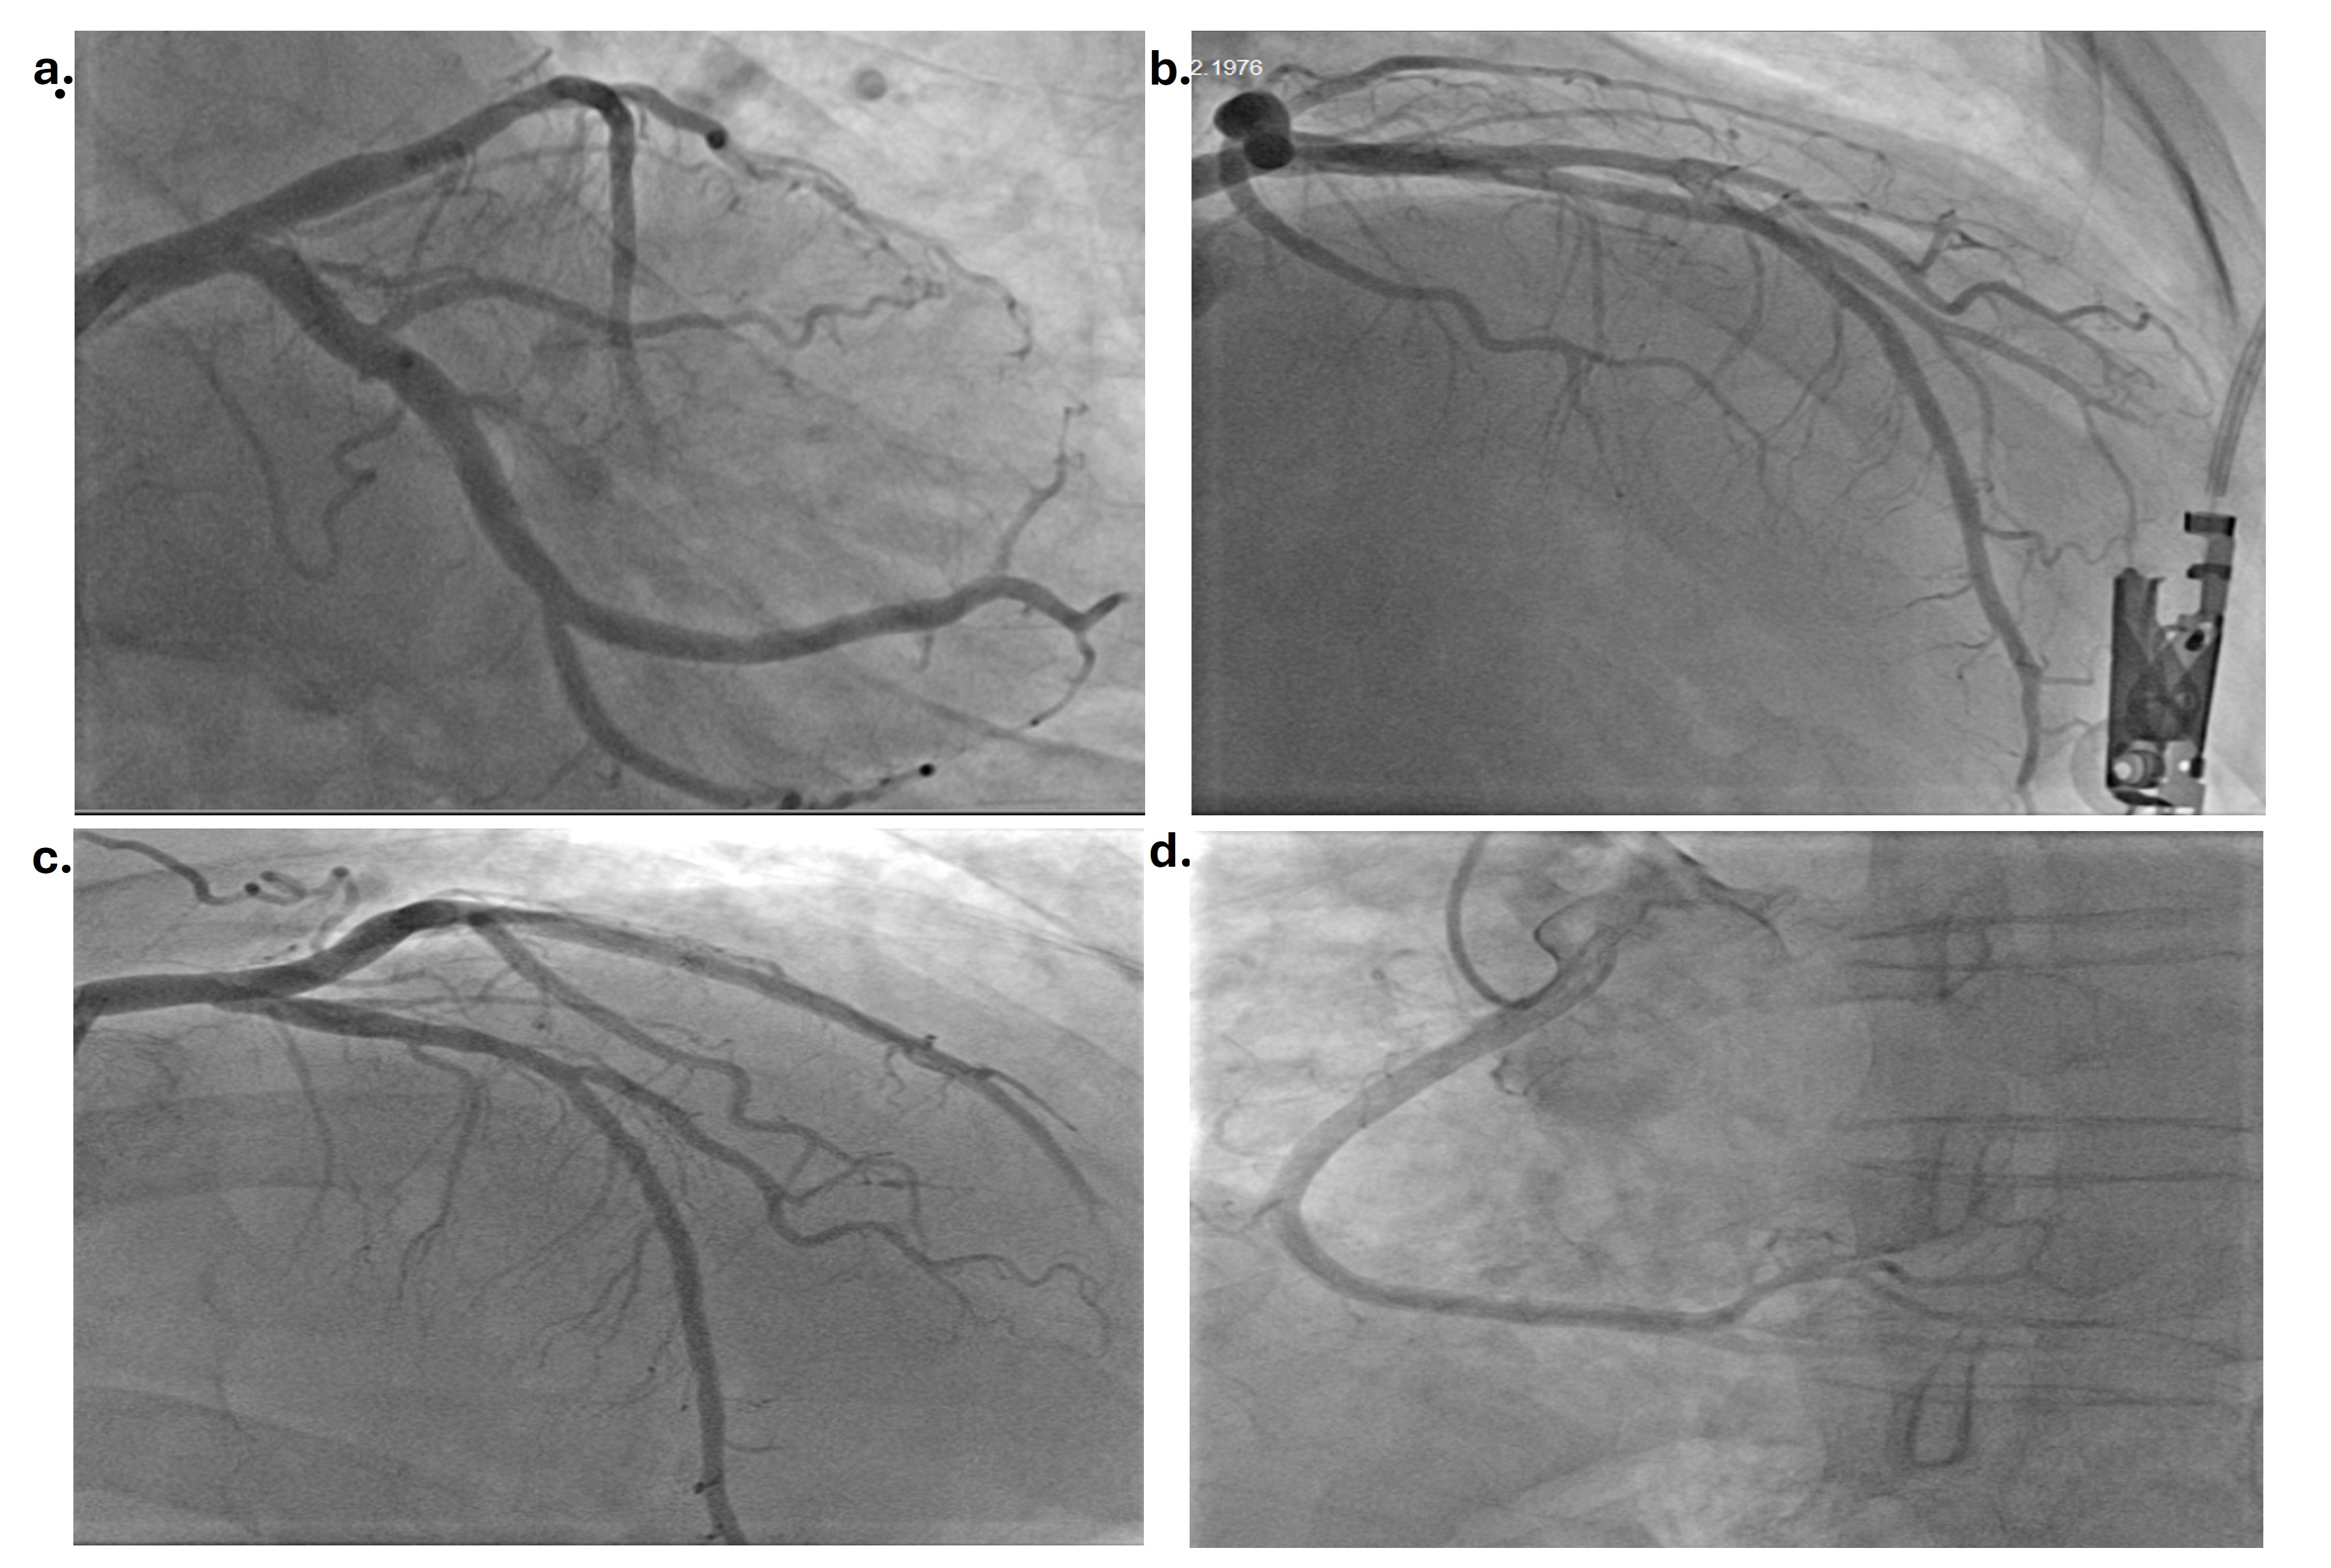

A 48-year-old man was admitted to the emergency department with chest pain after intense exercise in cold weather. There was no risk factor other than a history of hypertension. There was no history of smoking, alcohol, drug or substance use. Physical examination was normal. Electrocardiography (ECG) showed T inversion in the anterior, lateral and inferior leads with sinus rhythm (Figure 1). There were no abnormalities in the blood values other than elevated cardiac troponin I (cTnI 1100 ng/mL). Echocardiography revealed an ejection fraction of 42% and inferior, posterior, and lateral wall hypokinesis. Diagnostic coronary angiography revealed a 90% diffuse long stenosis in the proximal left anterior descending artery (LAD), subtotal stenosis in the mid-circumflex artery (Cx), and 99% stenosis in the first obtuse marginal artery and the normal right coronary artery (Figure 2, Video 1).